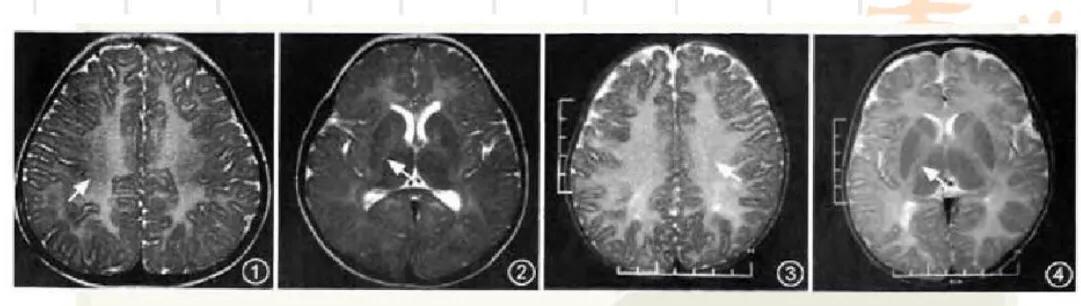

如果髓鞘化延迟特别明显,可以通过头部的磁共振判断髓鞘化的程度。如果神经髓鞘不能形成,或者显示髓鞘发育不良特别明显,同时有眼球震颤、肌张力低下、共济失调及进行性运动功能障碍,还要考虑佩梅病、Salla病等遗传病。